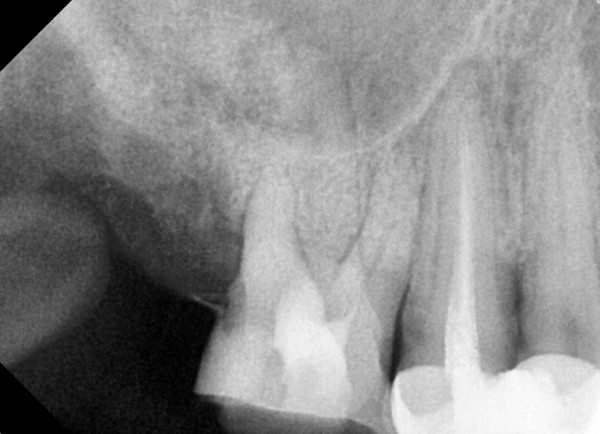

충치치료&신경치료 하루에 끝나는 신경치료

60bab75a1a70db4a6fd0ef2b4df1f9ae_1767342917_5257.jpg